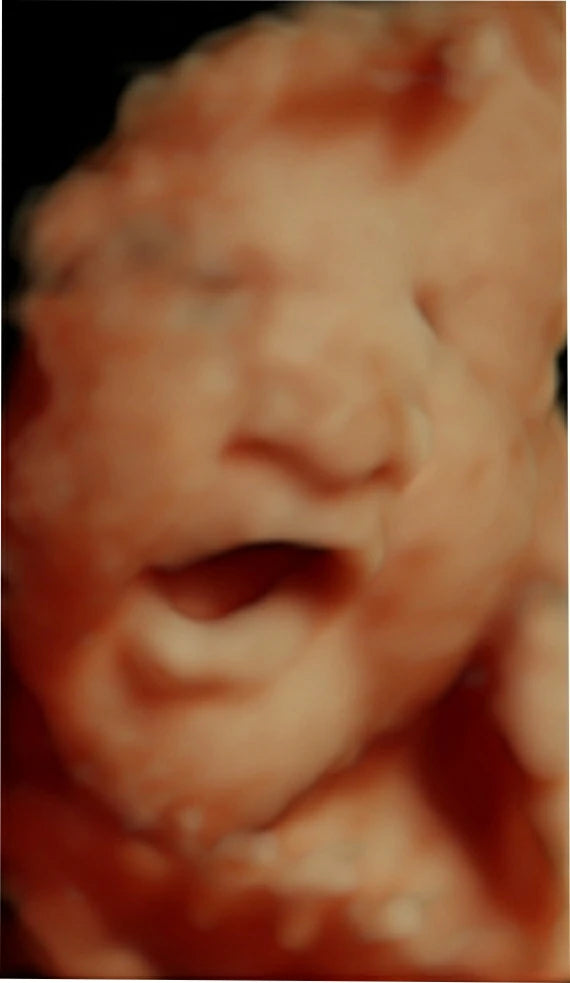

El ultrasonido obstétrico 4D HD es una innovadora técnica de imagenología que utiliza ondas de sonido para generar imágenes tridimensionales en alta definición de su bebé dentro del útero. Esta tecnología avanzada le permite observar los movimientos, gestos y rasgos faciales de su bebé en tiempo real, ofreciendo una experiencia emocionante y conmovedora durante el embarazo.

Imagen: Imagen de un bebé en el útero obtenida a través de un ultrasonido 4D HD.

Imágenes en alta definición y en tiempo real que permiten una visión detallada de su bebé.

Evaluación del desarrollo y la anatomía de su bebé en alta resolución para garantizar su bienestar.